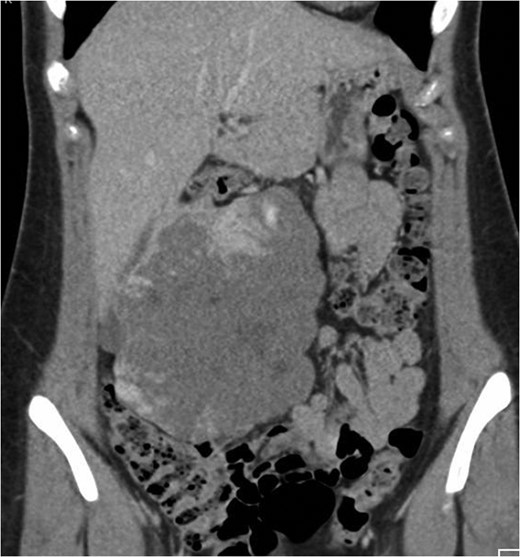

Coronal CT image in the portal venous phase demonstrating the large exophytic haemangioma.

Axial CT image in portal venou phase at level slightly inferior to aortic bifurcation demonstrating the peripheral nodular enhancement of the haemangioma.